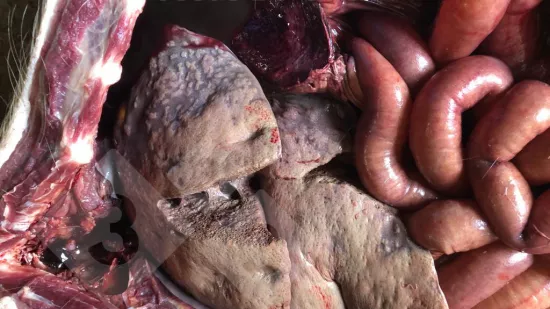

Quelle lésion peut être observée sur l’image ?